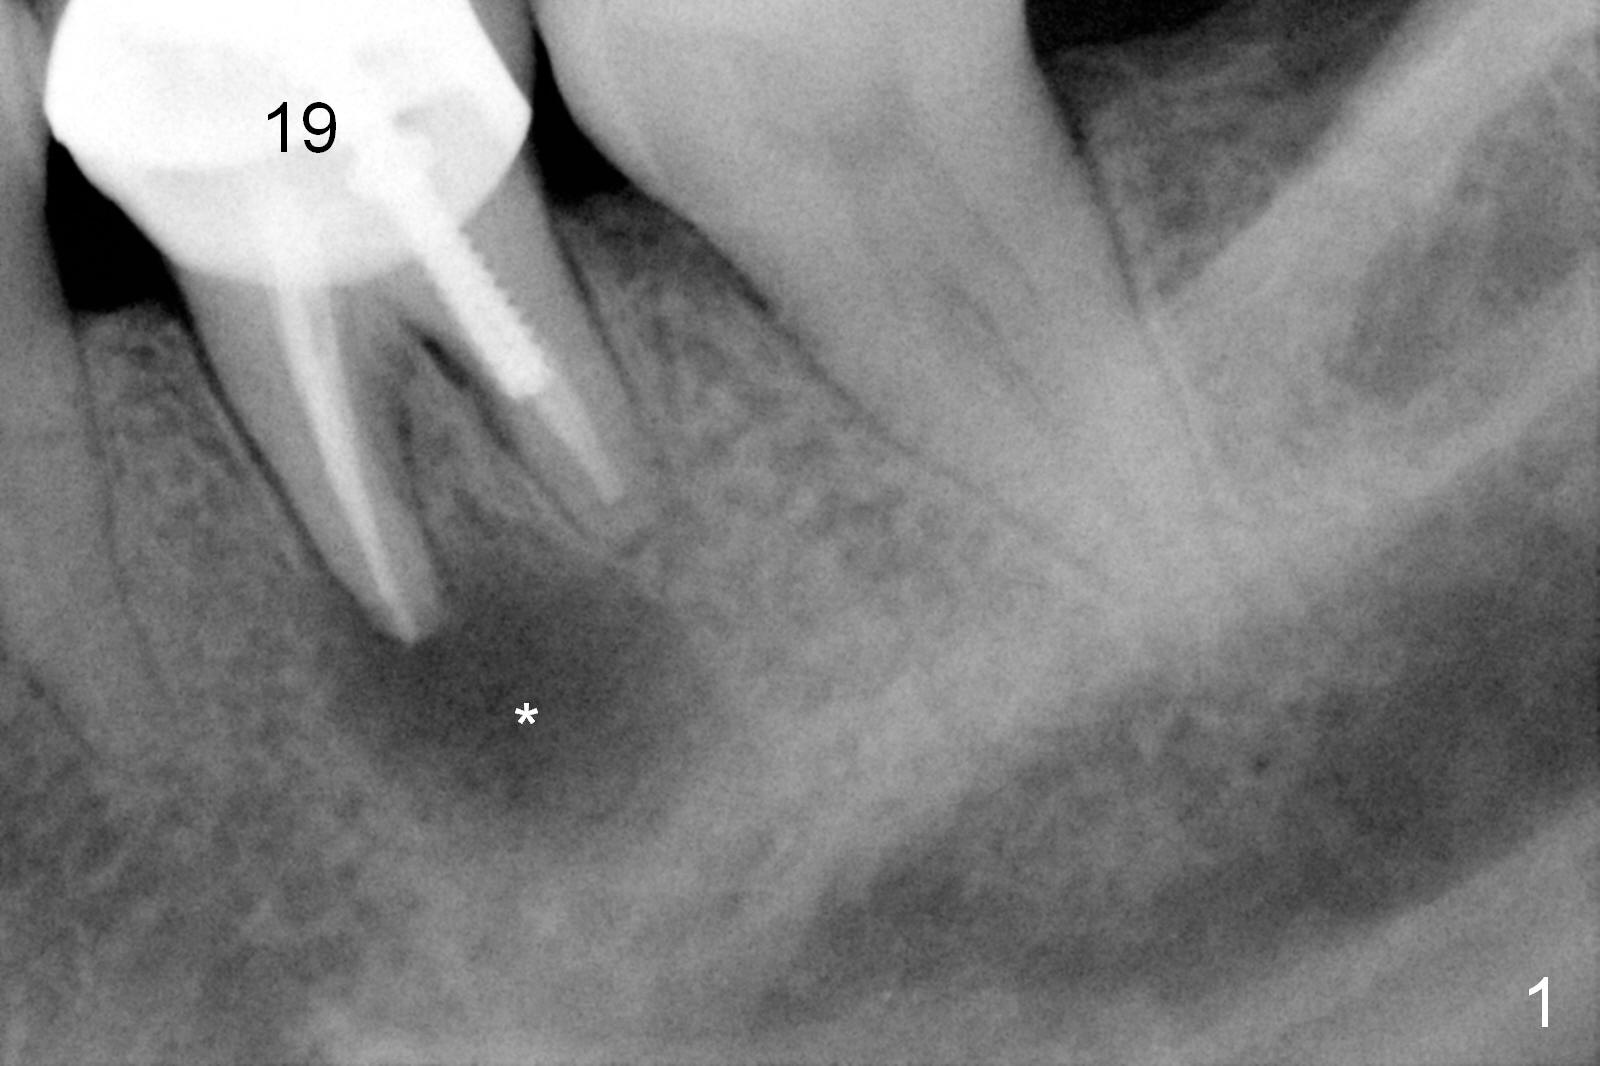

A 58-year-old lady has a long-standing periapical lesion with several episodes of acute infection (Fig.1-3, taken 10, 9 and 2 years ago, respectively). Explore the socket for size and wall integrity (Clindamycin). If the bony defect is not extensive, place a longest implant (18 mm bone-level, 20 mm tissue-level) with moderate diameter (5.5, 6 mm). Otherwise use a shorter, but wider tapered implant (7x12 mm (bone-level), 7 or 8x17 mm (tissue-level)). If the socket is extremely large, consider using 7 or 8 x20 mm cylindrical tissue-level implant. Use Bicon 2 mm pilot drill with extension to measure the socket depth and obtain 3-6 mm new bone or until 20 mm (gingival margin). Take PA. The 1st option is to use UF 3-4.7x18 mm drills at 50 RPM. Make sure that the depth is reached (septum crestal level) and check osteotomy wall integrity after each drill. Then place a 5 or 5.5x16 or 18 mm implant (Fig.6). The 2nd and 3rd options are shown in Fig.4 and 5. Due to severe infection and pain, a shorter implant is placed.